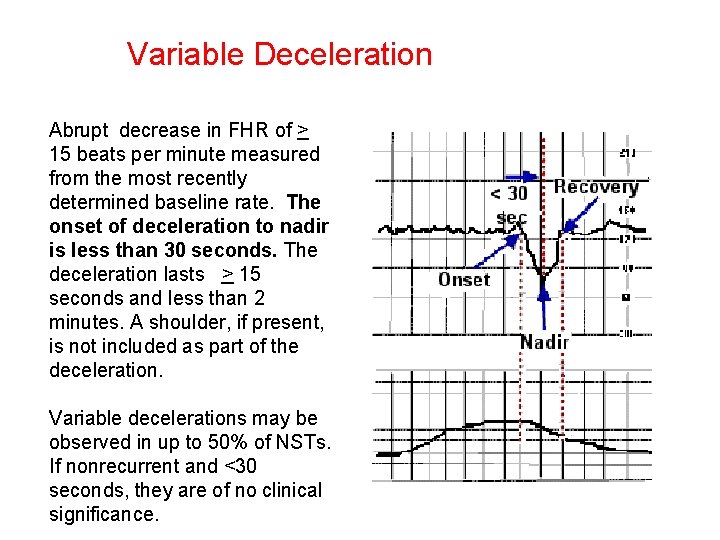

Variable Deceleration Abrupt decrease in FHR of > 15 beats per minute measured from the most recently determined baseline rate. The onset of deceleration to nadir is less than 30 seconds. The deceleration lasts > 15 seconds and less than 2 minutes. A shoulder, if present, is not included as part of the deceleration. Variable decelerations may be observed in up to 50% of NSTs. If nonrecurrent and <30 seconds, they are of no clinical significance.

Variable Deceleration Typical: • shoulders Atypical : • Overshoot • Loss of primary shoulder • Slow return to baseline (late component) • Baseline returns to a lower level(after deceleration) • Biphasic(W shape) • loss of variability during deceleration

Classification severity of variable deceleration • Mild: duration < 30 second or depth up to 80 bpm • Moderate : deceleration < 80 bpm • Severe : deceleration < 70 bpm for more than 60 second